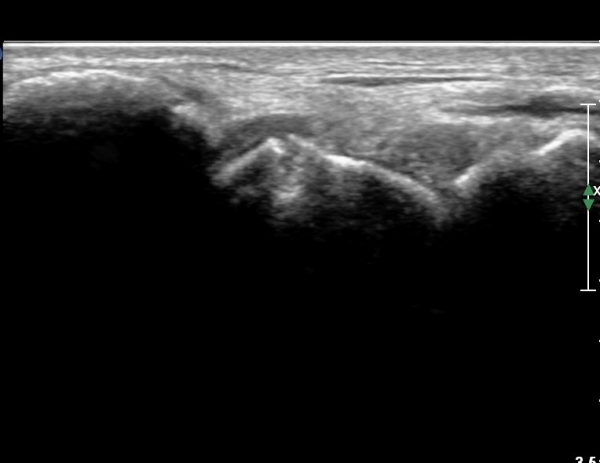

¼Õ¸ñ ¿ä°ñÃø ÁÖ»ó°ñ Á¾´Ü¸é °Ë»ç¿¡¼ ÁÖ»ó°ñ ÇÇÁú°ñ ¿¬¼Ó¼º ¼Ò½ÇÀÌ ¶Ñ·ÈÇÏ°í µ¿¹ÝµÈ ¿¬ºÎÁ¶Á÷ ºÎÁ¾ÀÌ °üÂûµÊ(»çÁø 3, 4)/

È®ÁøÀ» À§ÇÑ ÃÊÀ½ÆÄ°Ë»ç¿¡¼ ÁÖ»ó°ñ °ñÀý È®ÀÓ µÊ.